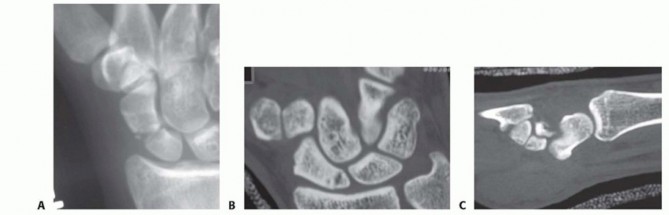

20 MIN READ Volar Wedge Bone Grafting and Internal Fixation of Scaphoid Nonunions يناير 2023 Read More